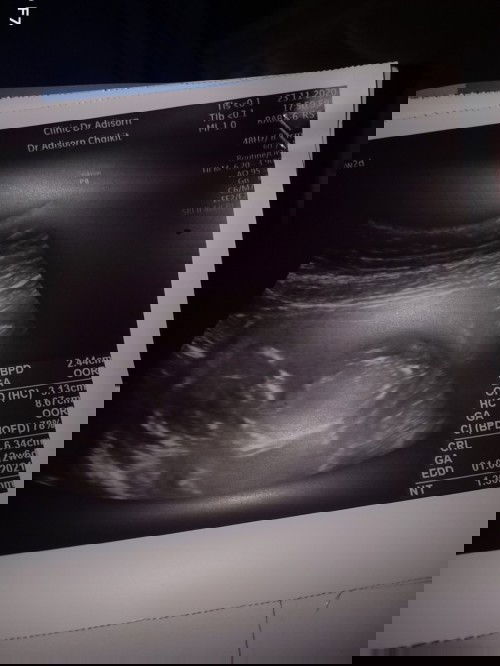

พอดูออกว่าเป็นเพศไหนคะ

#ขอคำแนะนำหน่อยค่ะ #ขอบคุณสำหรับคำตอบค่ะ #ท้องแรกคะ

พอดูเพศออกปาวคับหรือรออายุครรภ์มากกว่านี้ก่อน

#ท้องแรกคะ #ขอคำแนะนำหน่อยค่ะ

ชายค่ะ

6เดือนจะชัดเจนสุดค่ะ